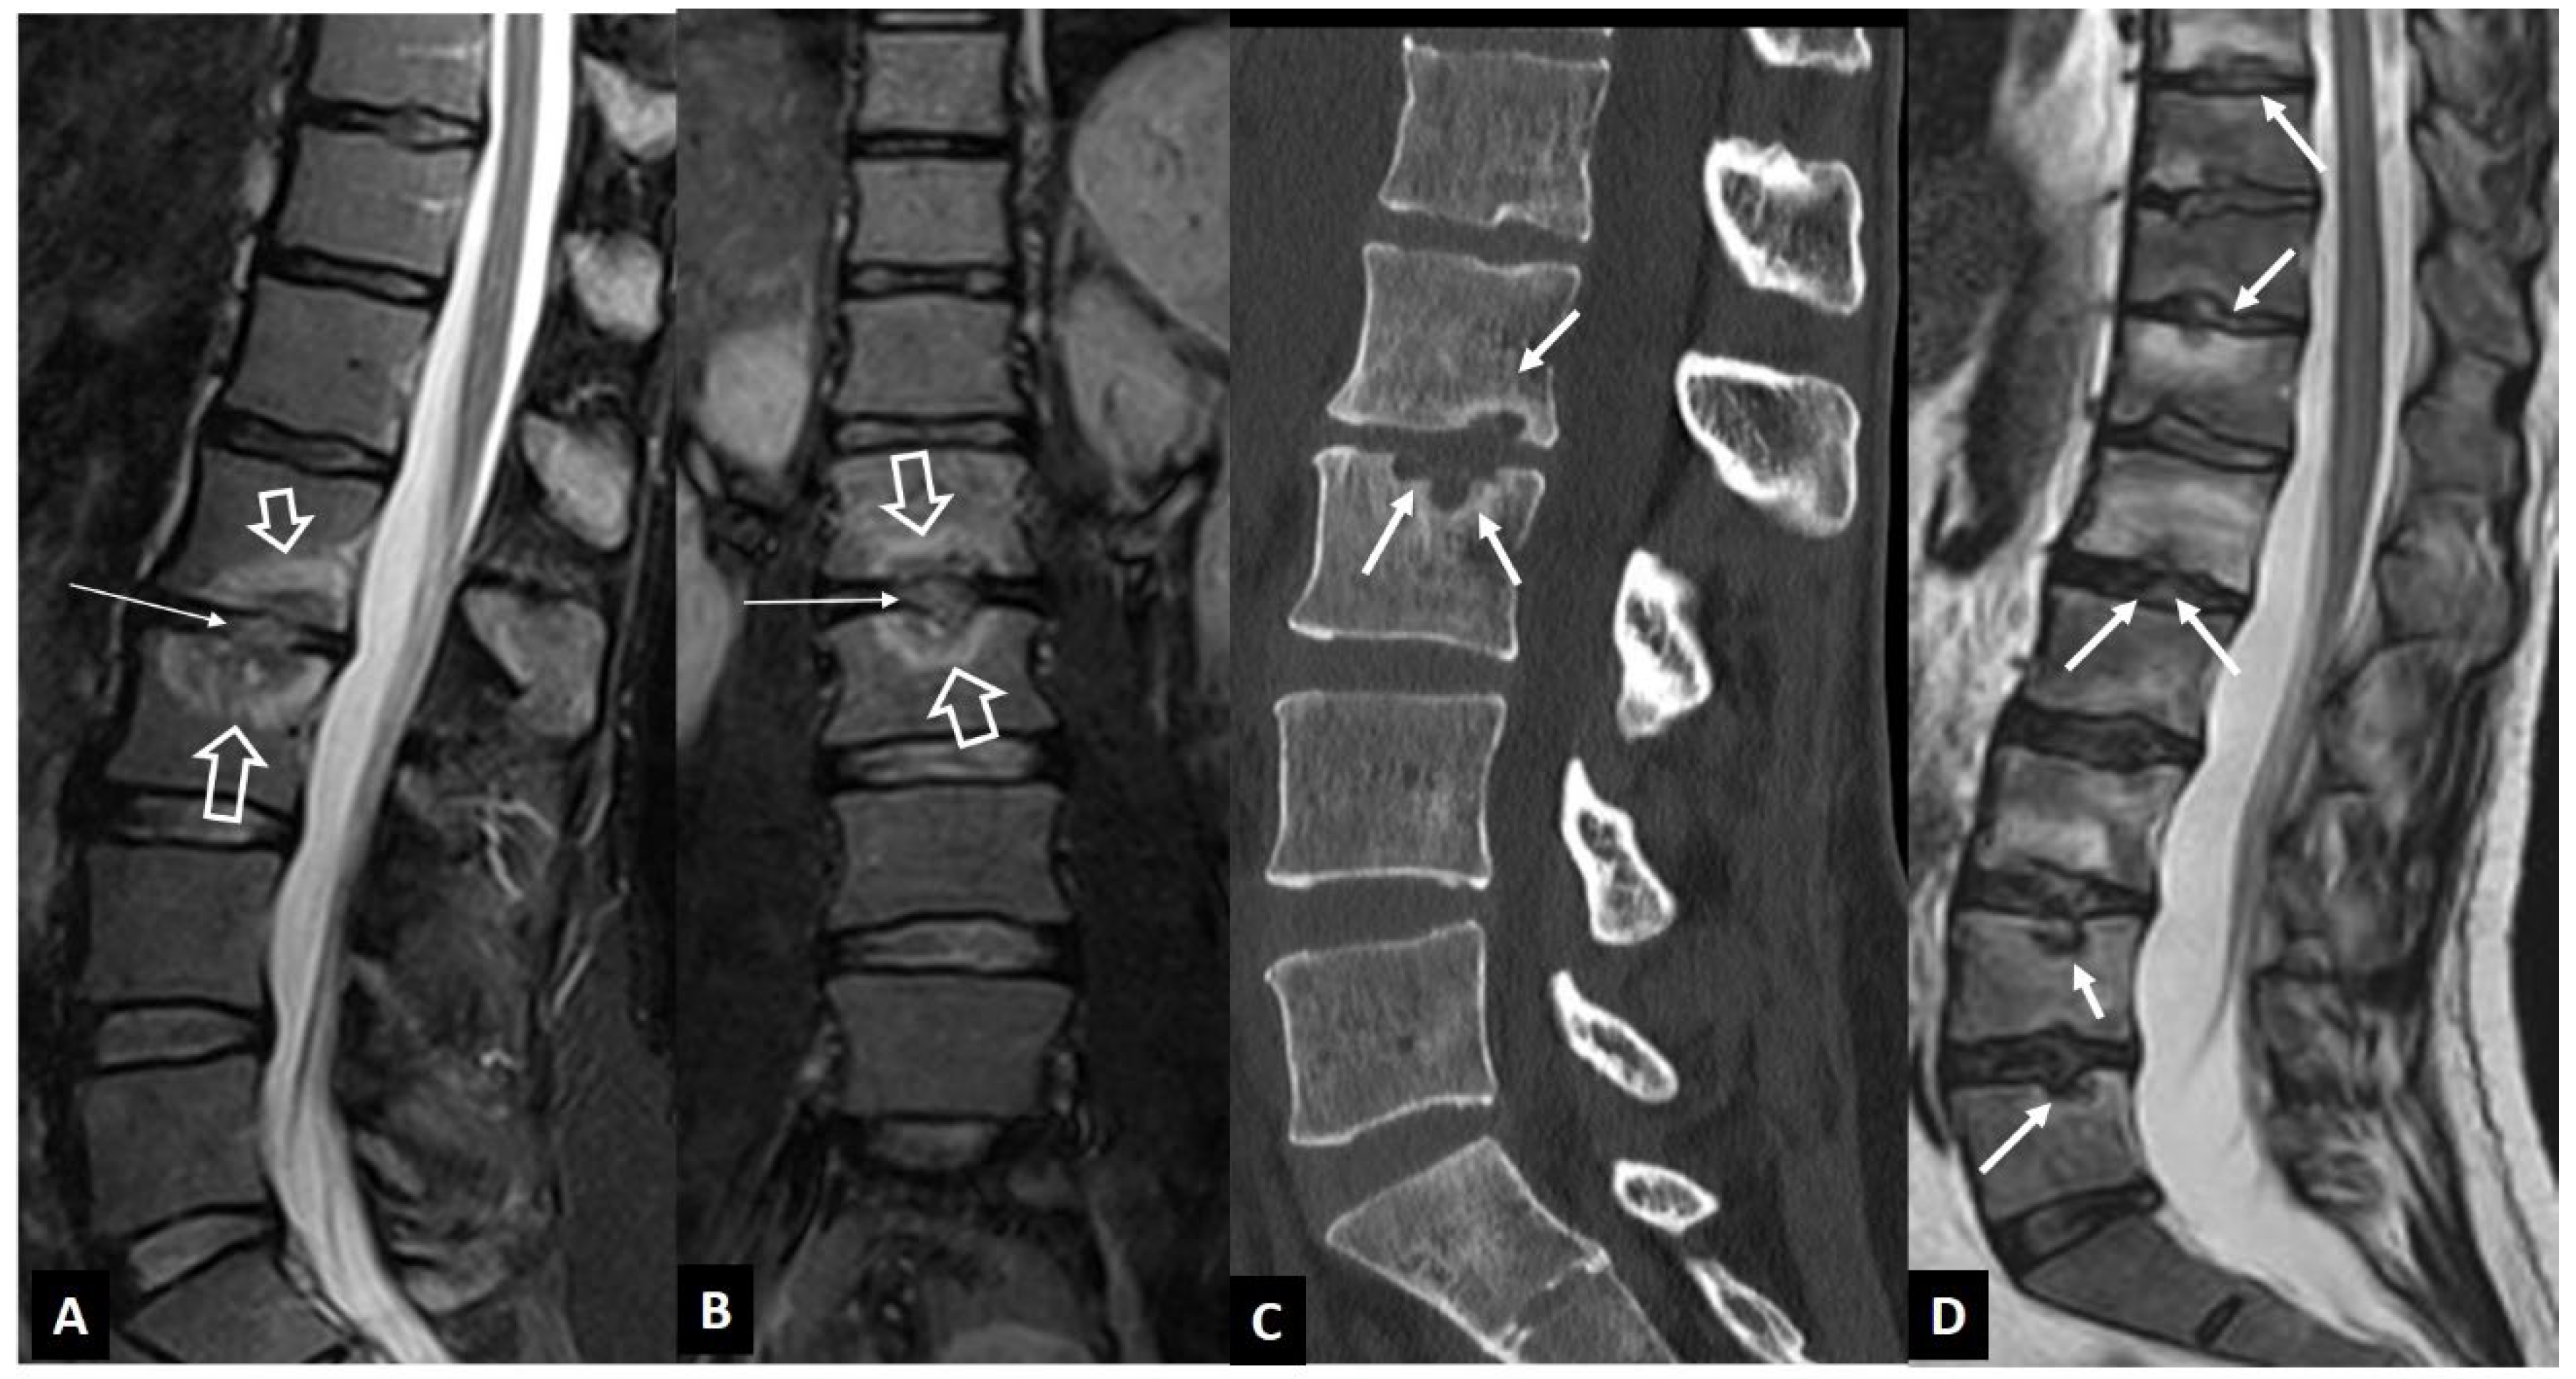

1. a.vi. Postop Aseptic Discitis

1. a.vii. Trauma

1. a.viii. Rheumatoid Arthritis